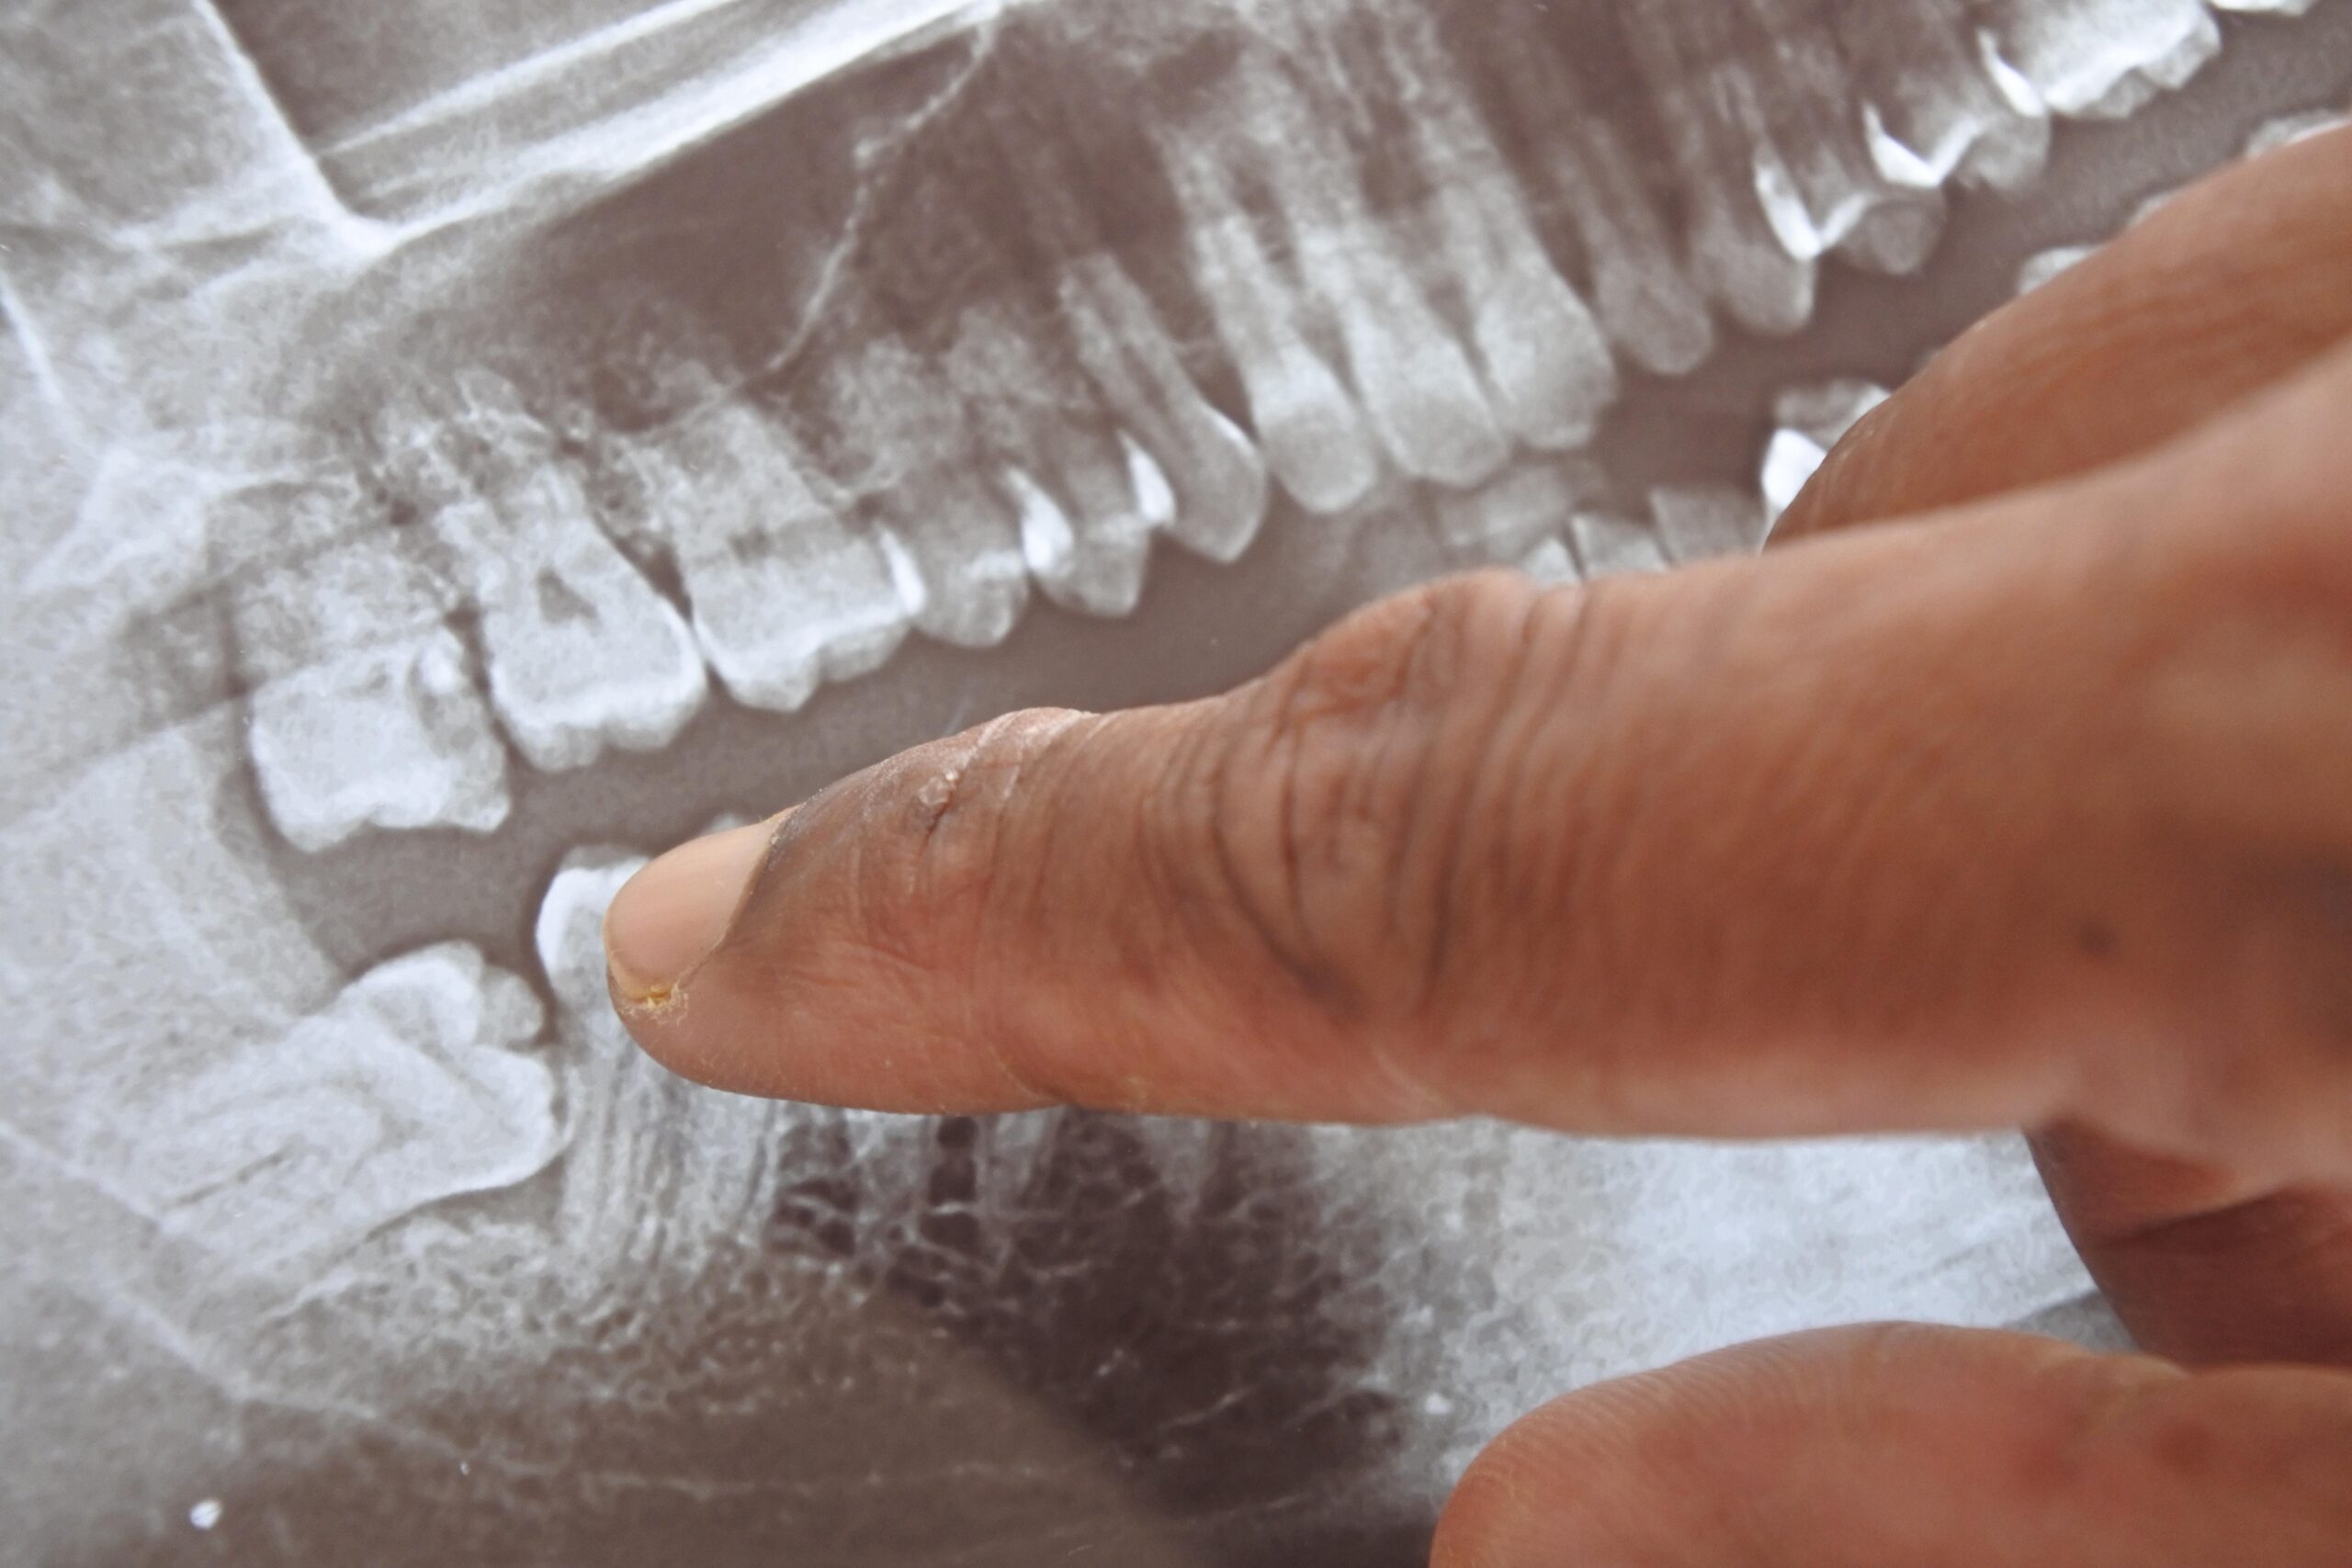

A tooth may need to be pulled due to severe decay, infection, overcrowding, or damage beyond repair, ensuring oral health and preventing further complications or pain

When a tooth becomes severely infected, heavily decayed, or structurally compromised, leaving it in place puts your neighboring teeth at serious risk. Bacteria can spread from a single infected tooth into your gum tissue and jawbone, leading to severe complications. By removing a compromised tooth, you stop the spread of disease and preserve the healthy foundation of your smile.